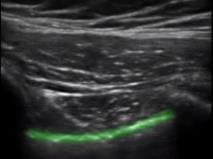

Bild: Lunge, Pleuralinie

Markierter Bereich: Pleuralinie